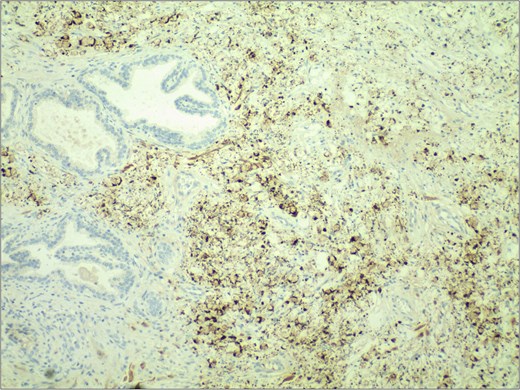

In November 2024, the patient presented with progressive dysuria for 3 years, accompanied by recurrent urinary retention for 3 weeks. Physical examination revealed a prostate enlarged to grade II, with a firm texture, smooth surface, no palpable nodules, no tenderness, a shallow median sulcus, and no sphincter relaxation. Imaging studies with 3.0 T prostate magnetic resonance imaging (MRI) showed a prostate measuring ⁓5.7 × 4.8 × 5.7 cm, with marked enlargement of the transition zone and heterogeneous signals. Small, patchy short T2 signals were internally observed, along with slightly high diffusion-weighted imaging (DWI) signals and slightly decreased apparent diffusion coefficient (ADC) signals, yielding a PI-RADS score of 3. The peripheral zone was thinned and indistinct. The seminal vesicles showed normal size and morphology, and the bladder-seminal vesicle triangle was intact. No enlarged lymph nodes were evident in the pelvic cavity. Laboratory tests showed a total prostate-specific antigen level of 1.759 ng/ml. Initially diagnosed with benign prostatic hyperplasia, the patient underwent transurethral enucleation of the prostate with a thulium laser under general anesthesia on 19 November 2024. The surgery was successful. Postoperative pathology indicated poorly differentiated adenocarcinoma, predominantly signet ring cell carcinoma, presumed to be of gastric origin (Fig. 1). Immunohistochemical analysis revealed negativity for prostate cancer markers (PSA and P504S) and positivity for gastrointestinal tumor markers [CKP(3+), CK20(+), CEA(3+), Villin(2+), CDX-2(2+)] (Fig. 2). Morphological comparison with previous gastric cancer pathology slides showed similar features, confirming metastatic gastric signet ring cell carcinoma to the prostate. The patient continued chemotherapy with the original gastric cancer regimen postoperatively and is currently under follow-up.

Immunohistochemical staining demonstrated strong positivity (++) for villin in the cytoplasm and cell membrane of tumor cells. IHC stain 40×.

Most cases of secondary prostate cancer arise from direct infiltration by tumors in adjacent organs, with only ⁓1% resulting from distant primary cancers other than leukemia or lymphoma [7]. In this case, the most probable route of metastasis from gastric cancer to the prostate is through a specific hematogenous spread [8]. The diagnosis and treatment of secondary prostate signet ring cell carcinoma pose significant challenges [9]. Due to its rarity, clinical awareness of this prostate cancer subtype is insufficient, potentially leading to misdiagnosis or missed diagnosis. Diagnostic accuracy currently relies on histopathological and immunohistochemical examinations, coupled with a history of related tumors [10]. In this case, histopathological examination of the prostate tissue revealed signet ring cell carcinoma, showing morphological similarities to previous gastric cancer pathology slides. Further immunohistochemical analysis confirmed the absence of prostate cancer markers (PSA and P504S) and the presence of gastrointestinal tumor markers [CKP(3+), CK20(+), CEA(3+), Villin(2+), CDX-2(2+)], definitively diagnosing the case as secondary prostate signet ring cell carcinoma.